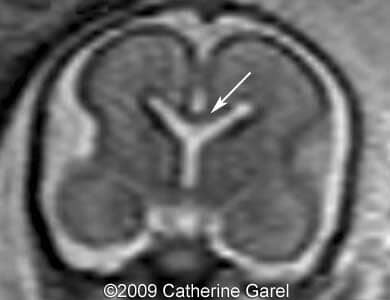

Images 7,8: MRI Image 7 shows a wavy midline structure which was detected on the ultrasound images (Images 4,6), the structure is hypodense on the MRI images. Image 8 shows an interhemispheric fissure in the anterior and posterior region.

Case262_7

Case262_8

Images 9,10: Images 9, 10 show a fusion in the posterior frontal and parietal regions, indicated by arrows.

Case262_9a

Case262_10a